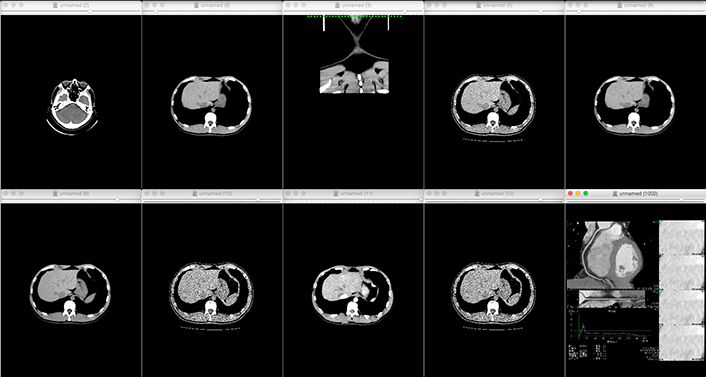

- Reads DICOM data obtained from CT imaging into mimics

- Eliminates noise (artifacts) generated by metal and other materials

-

We will convert the data into 3D data

and confirm with the customer that

the area of interest has been reproduced in the image or data.*If the STL output is available directly from the medical workstation,

the above process is eliminated. - 3D printing output